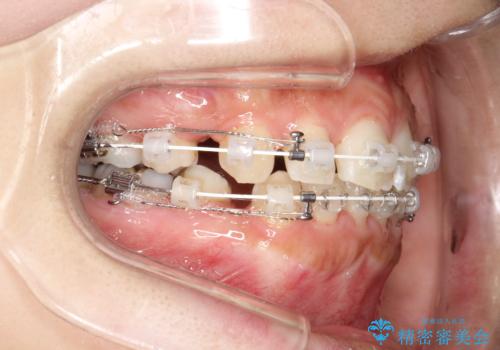

- 審美装置

- 2年2ヶ月

- 口元が出てるのが気になるとのことで来院されました。

上下左右前から4番目の歯を抜歯して前歯を後方に下げて、口元を下げる計画としました。